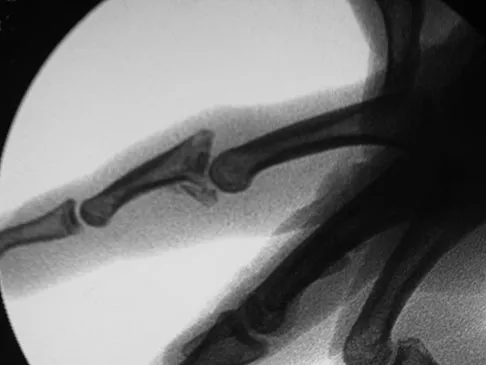

Question 55

Figures 23a and 23b show the radiograph and clinical photograph of a patient who reports a reduced ability to flex the interphalangeal joint of her great toe after undergoing a Chevron-Akin bunionectomy. What is the most likely cause?

Explanation